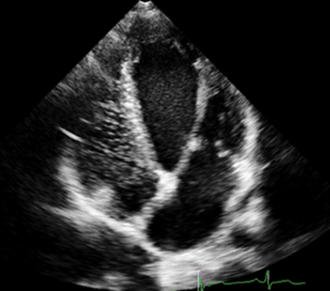

右心超声造影的临床应用价值

经静脉注射能随血液流动的“微气泡”,如:震荡生理盐水,造影剂微泡直径大(>70um),不能通过肺循环,只能在右房、右室显影,称之右心超声造影。

右心超声造影能够诊断分流性先心病:如房间隔缺损、卵圆孔未闭(PFO)等;协助诊断某些先心病:如永存左上腔,肺动静脉瘘等;了解右心大小,心内膜情况,室壁厚度,心腔有无占位,瓣膜反流等;记录臂心循环时间,了解心功能。

总之,右心超声造影是二维和彩色多普勒超声心动图的有益补充,可以敏感、准确地诊断一些常规超声心动图无法确定的先天性心脏病,对判定心内、心外的左向右、右向左分流及解剖学右心房有着不可替代的诊断价值。